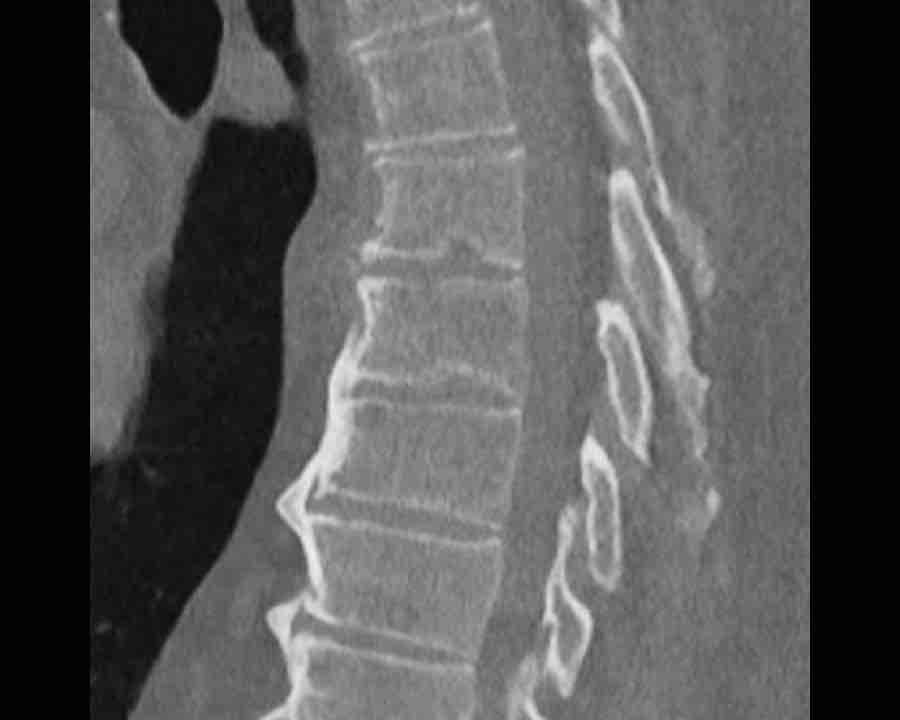

Scroll through images.

What are the findings?

Findings

- C injury? No.

- Signs of a rigid spine?

Yes, a B3 injury is very likely. - A subtle fracture on the anterior vertebral body.

Conclusion

Injury type B3.